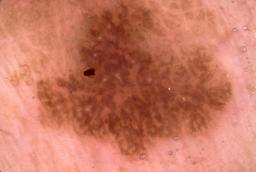

{

"age_approx": 75,

"anatom_site_general": "head/neck",

"concomitant_biopsy": true,

"dermoscopic_type": "contact non-polarized",

"diagnosis_1": "Benign",

"diagnosis_2": "Benign epidermal proliferations",

"diagnosis_3": "Seborrheic keratosis",

"diagnosis_confirm_type": "histopathology",

"image_type": "dermoscopic",

"lesion_id": "IL_5213308",

"patient_id": "IP_4497472",

"sex": "male"

}